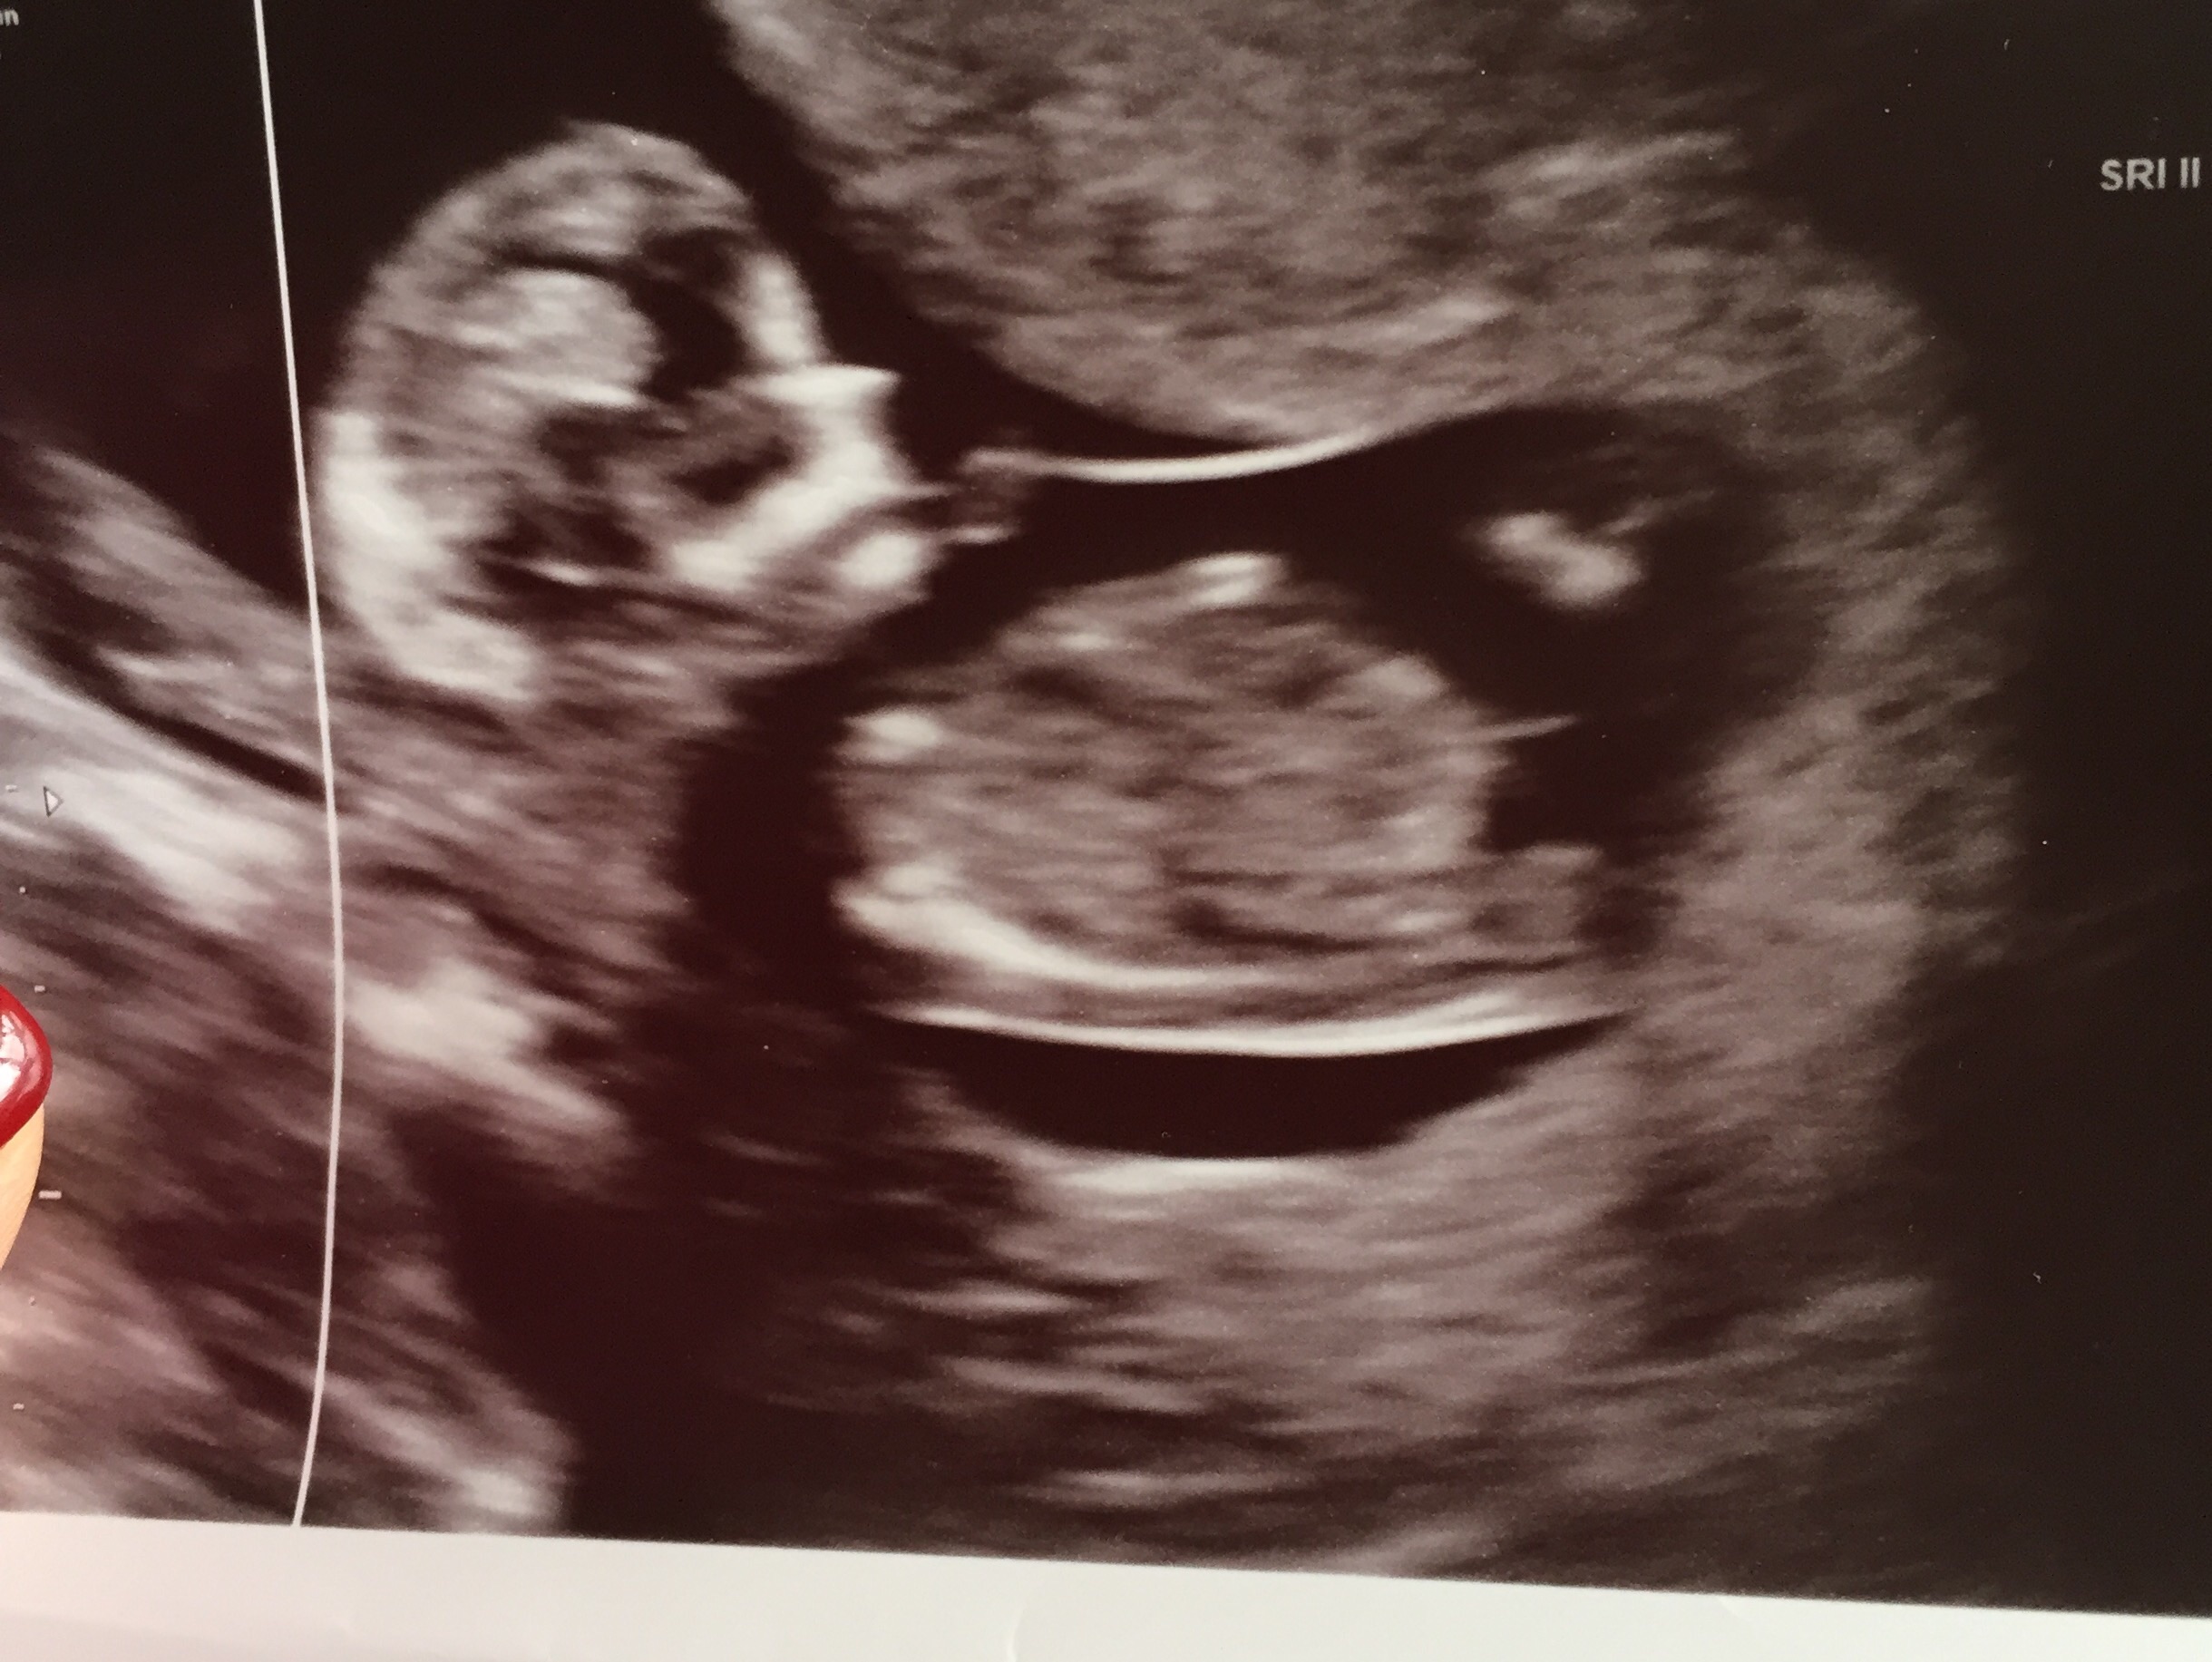

Hi, I'm new to this site and need some help with nub theory. I've had my 12 wk scan and have been googling nub theory. I've looked at my pic and I can see two lines one near the genital area up from the spine and one closer to the belly. Uploaded my scan pic can anyone help please??Which one is the nub??Attachment 30909

Lower near where legs are/would be-- not sure I can make this one out.

Nub isn't visible in this pic.